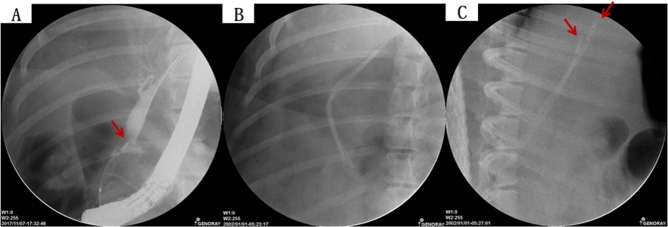

Fluoroscopic analysis via ERCP and blood analysis

In all six swine animal models, we succeeded in generating BSS using intraductal RFA without any complications such as bleeding or perforation (success rate = 100% (6/6), severe complication rate = 0%). Blood levels of WBC, AST, ALT, ALP, GGT, and CRP of all experimental animals were measured before the intraductal RFA procedure, after the intraductal RFA procedure (2 weeks after RFA), and before euthanizing animals (Figs. 1, 2, 3A–G). Blood levels of WBC, AST, ALT, ALP, GGT, and CRP were elevated after the intraductal RFA procedure but decreased after biliary stenting. Figure 1H,I are biliary fluoroscopy findings at 2 weeks after RFA in experimental animals 1 and 2, demonstrating biliary stenosis. The same trend of blood test results as in Fig. 1 was observed in Fig. 2. The difference between Figs. 1 and 2 was that the follow-up was performed at 3 months after biliary stenting in Fig. 2. Biliary stenosis was confirmed by fluoroscopy findings at 2 weeks after RFA in experimental animals 3 and 4 (Fig. 2H,I). Experimental animals 5 and 6 were followed for 5 months after biliary stenting. They showed the same tendency of blood test results (Fig. 3A–G). Biliary stenosis was also confirmed by fluoroscopy findings at 2 weeks after RFA in experimental animals 5 and 6 (Fig. 3H,I).

Confirmation of biliary stenosis in experimental animals and insertion of plastic stents

After 2 weeks of intraductal RFA, ERCP was performed to confirm biliary stenosis of treated experimental animals. Blood tests including White Blood Cell (WBC), Aspartate Transaminase (AST), Alanine Transaminase (ALT), Alkaline Phosphatase (ALP), Gamma-Glutamyl Transferase (GGT) and C-Reactive Protein (CRP) were performed before the procedure, after the procedure, and at the final follow-up. Using a 0.035-inch guidewire (Hydrophilic Tipped Guidewire, Boston Scientific Corp., Natick, MA, USA) under fluoroscopy, two commercially available 10-F biliary plastic stents (polyurethane tube of outer diameter 3.3 mm and inner diameter 2.0 mm; polyethylene tubing of outer diameter 3.3 mm and inner diameter 2.0 mm) were placed in the biliary tract (Fig. 7). The proximal end of the plastic stent was mounted to be located in the intrahepatic bile ducts of different branches (Fig. 7C).